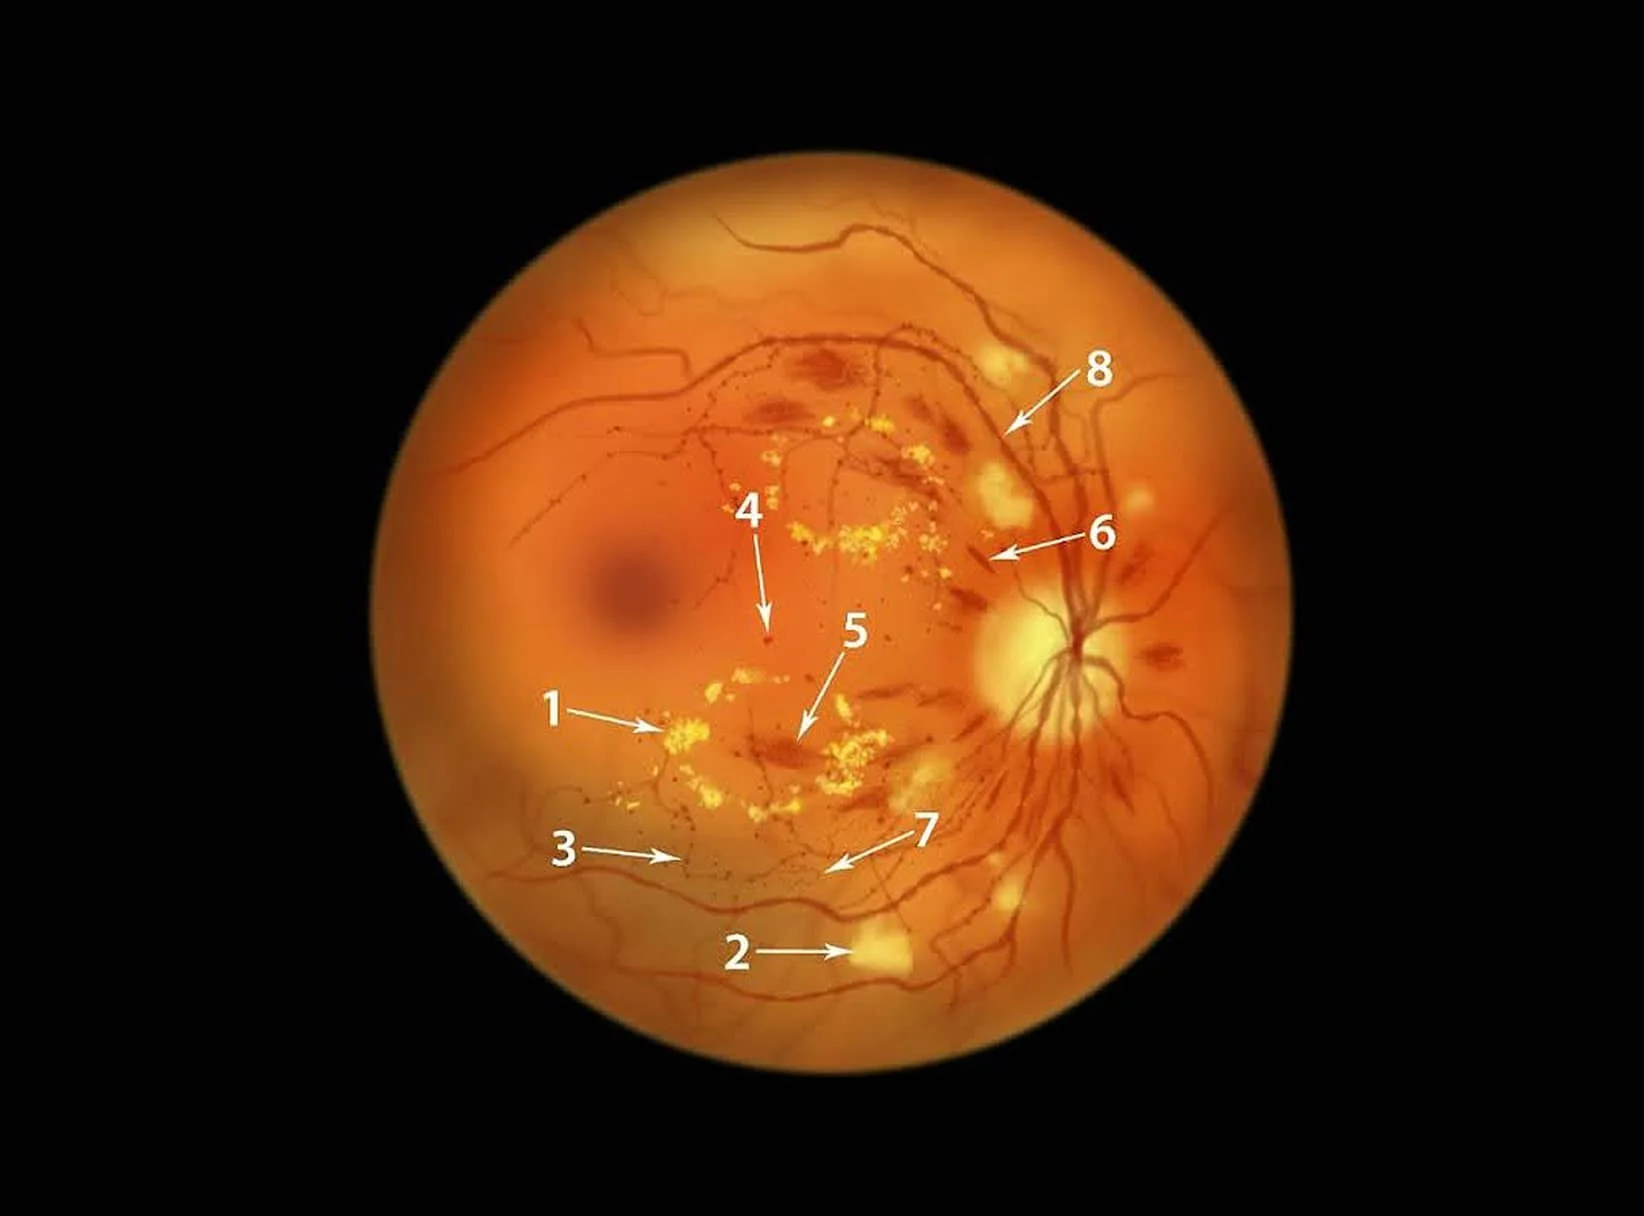

Diabetic Retinopathy

Diabetes can harm the retina by reducing blood flow, leading to serious damage and vision problems if untreated.